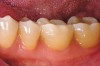

Figure 6c  The final restoration addresses the occlusal, proximal, and lingual compromises of the tooth yet preserves facial tooth structure.

Figure 6c

Figure 6e  A 2 mm facial chamfer provides an acceptable framework in which to optically blend the tooth/ceramic interface.

Figure 6e